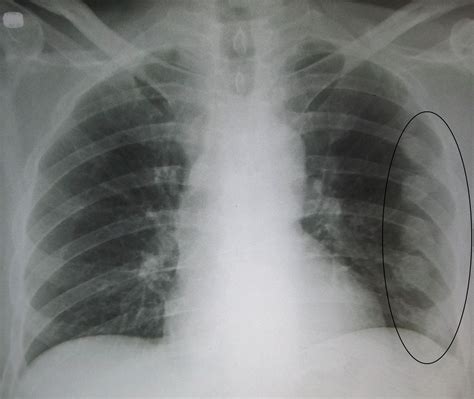

Ribs Under Breast Feel Bruised at Roxanne Corley blog